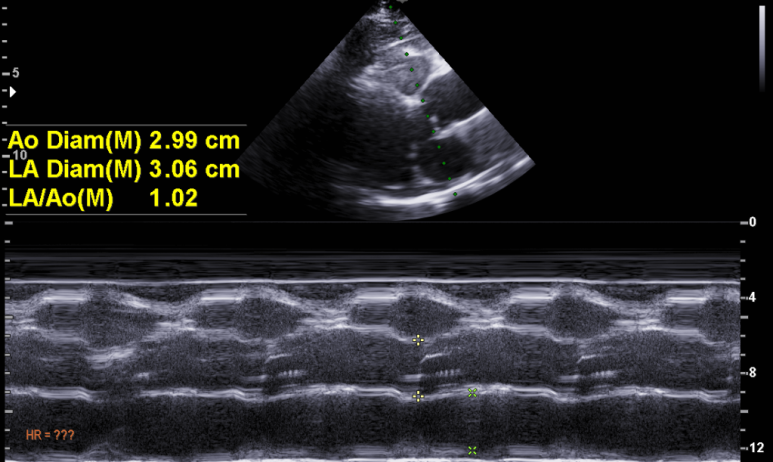

심초음파 검사; 초음파창이 좋지 않아 검사에 제한이 있다.

좌심방은 확장되어 있지 않음

심실벽이나 심실의 비대/확장은 없으며

수축기 기능은 정상